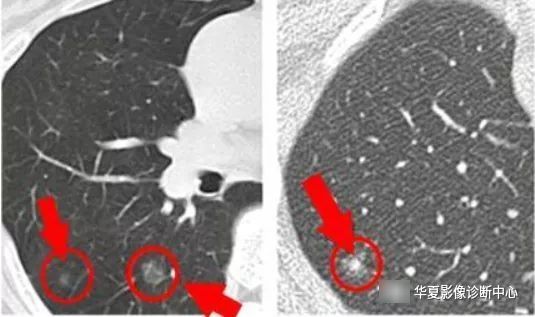

3、孤立的部分实性密度GGO,特别是实性成分大于5 mm者,3月后复查,发现病变增大或无变化时,应考虑恶性病变可能。一组资料显示,部分实性密度结节,恶性的可能性为63%,而纯的GGO为18%。大的纯GGO大多数为侵袭性病变。女性和年轻患者常为炎症。不推荐CT引导穿刺。术式推荐胸腔镜楔形手术或肺段切除,不推荐肺叶切除。